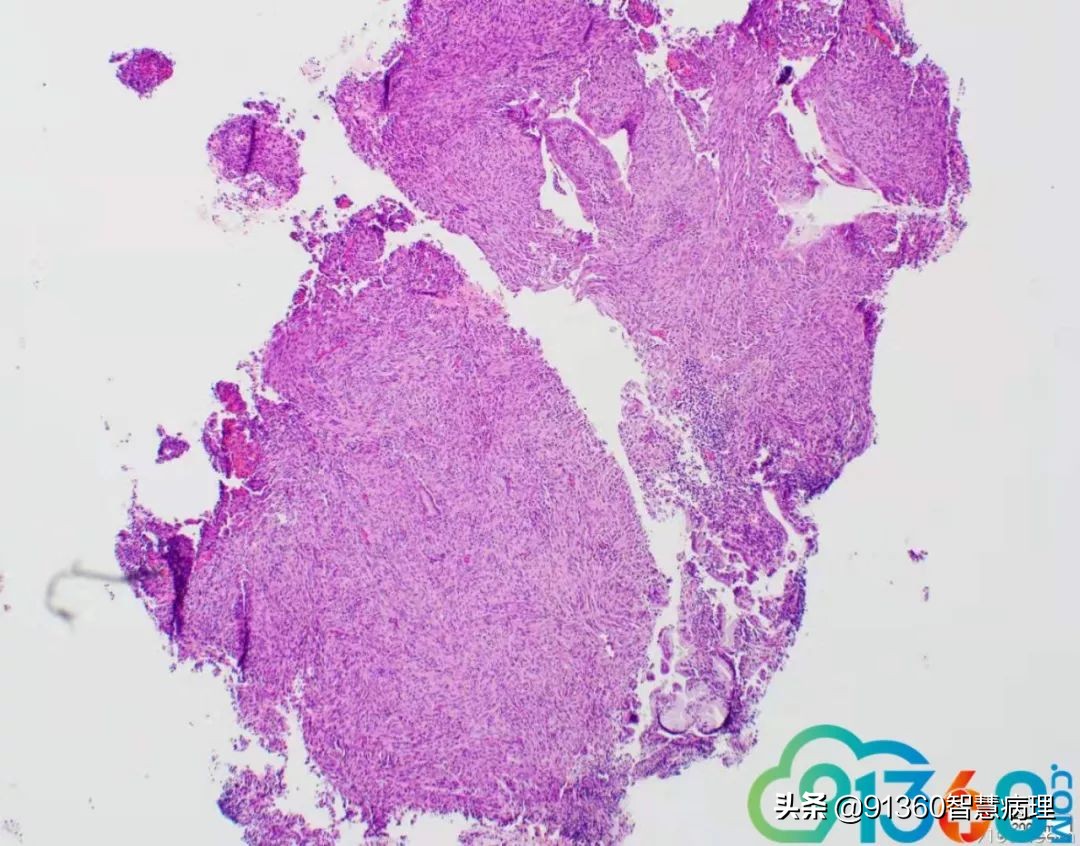

邢德印 39岁,宫颈活检 石岩 腺肉? 任永昌 梭形细胞恶性肿瘤,肉瘤首考,肉瘤样癌次之! 郭晓静 @邢德印(妇科病理)邢老师, 周末好!您的病例肯定有难度谢谢分享!抛砖引玉,我说下自己看法。1.39岁,为什么要活检?hpv情况和液基肯定有问题2.低倍这一点给我的感觉是有异型,其他很多似乎很弥漫,没有找到鳞状上皮,梭形细胞样

郭晓静 3.粘液上皮并没有小叶状结构,分散零散,最左边也就是放大倍数的 我感觉是有异型性的4.所以,是鳞的病变还是腺的病变,还是合并?还是梭形细胞间叶源性的病变~~我没有把握 但腺肉瘤的话,我感觉是不是要看到低倍的袖套样结构呢? 期待老师讲解!谢谢分享!